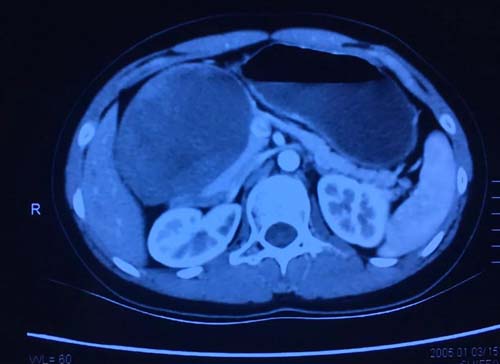

一名15岁少女因发现右上腹包块3月入住医院,无明显不适症状。查体显示右上腹肋缘下可触及肿块,大小约10cm×8cm。腹部强化CT结果为:胰头区占位,考虑实性假乳头状瘤可能性大。由于患者年龄小,肿瘤虽然巨大,考虑为良性可能性大。经过综合考虑,刘军主任确定为其行腹腔镜保留十二指肠的胰头切除术。刘军主任团队团结协作,克服术中各种困难,在保护好十二指肠的各支供应血管前提下,完整切除肿瘤,成功完成该手术。患者恢复顺利,术后6天出院!